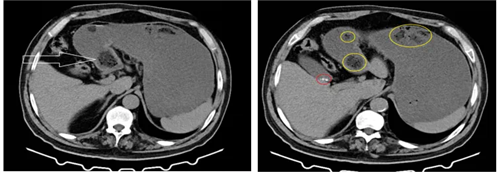

CT表现为边界清晰的椭圆形低密度肿块,斑驳的肿块外观是由于肿块间隙内留有气泡所致。

患者男,70岁,进食山楂后出现胃脘部持续性隐痛不适,伴恶心、呕吐,呕吐物为胃内容物,反酸、烧心。CT图示:胃内大量液体影,胃腔扩张,图1箭头示胃石影像,图2黄色圈-胃石,红色圈-胆囊高密度结石。